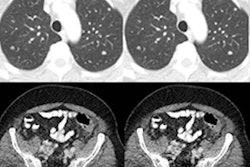

The widespread implementation of CT lung cancer screening in Europe appears to be on the horizon. New results from randomized controlled screening trials throughout the continent consistently supply mounting evidence for the test's potential benefits.

Recent results from the German Lung Cancer Screening Intervention (LUSI) trial continue the trend. The extent to which CT lung screening reduced cancer mortality risk for LUSI trial participants, particularly for female smokers, is the focal point of this edition's Insider Exclusive.

- Employing deep-learning algorithms, such as the artificial intelligence model developed by Google, to assess cancer risk on lung CT scans and predict lung cancer survival